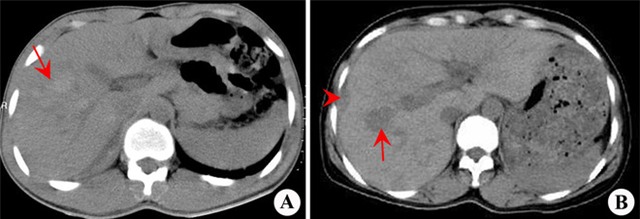

Sau khi khám bệnh, Giáo sư, bác sĩ Trình Lương Bân, trưởng khoa Gan, Bệnh viện Gan hạch – người trực tiếp chẩn đoán bệnh cho bà Trương cho biết, bà đã bị phù gan.

Bác sĩ Bân cho biết bệnh đang trong giai đoạn khởi đầu cấp tính, trong một thời gian ngắn mà gan đã phù nề nghiêm trọng.

Sau khi biết rõ nguyên nhân, may mắn thay các bác sĩ đã lập tức lên phương án điều trị chứng giảm phù gan, uống thuốc lợi tiểu bằng các phương pháp Đông Tây y kết hợp, lượng nước trong gan đã được giảm nhẹ.

Quá trình điều trị tích cực giúp bệnh tình của bà Trương về cơ bản được kiểm soát và không còn nguy hiểm đến tính mạng.

Trong loại tam thất đất này có thể có chứa chất alkaloid pyrrolidine, các chất độc hại, vì thế chúng là nguyên nhân gây ra chứng tiểu tĩnh mạch gan bị tắc nghẽn.

Chất alkaloid pyrrolidin gây độc cho gan, có thể gây ra tổn thương cho các tế bào gan, xoang gan và tiểu tĩnh mạch, nội mô, trường hợp nặng có thể phải bị yêu cầu ghép gan, thay gan.